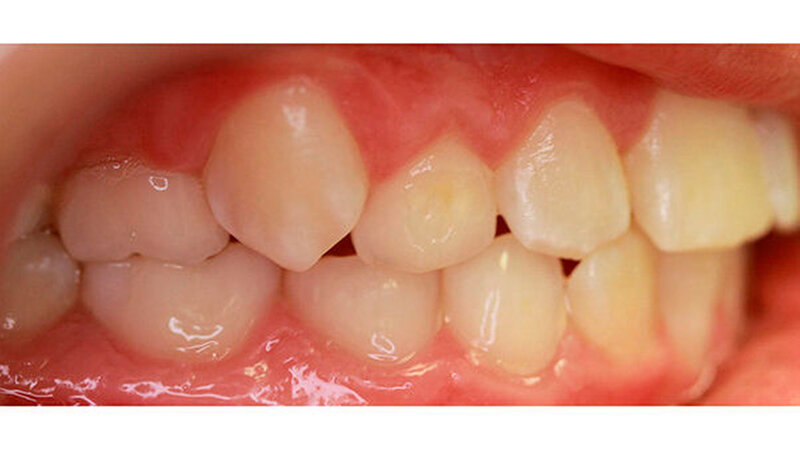

Im Rahmen der Modellanalyse ergaben sich folgende Befunde: Im Oberkiefer lagen außer der Transposition der Zähne 13 und 14 multiple Rotationen und Kippstände vor. Die Unterkieferfront wies einen Engstand auf. Im Molarenbereich lag beidseits eine Distalokklusion von ¼ Prämolarenbreite vor. Der Overjet betrug 2 mm, der Overbite 3 mm. Die Zähne 22/33, sowie 24/74 wiesen eine Kopfbissrelation auf.

Nach dreijähriger kieferorthopädischer Behandlung konnte die Patientin entbändert werden. Eine Stabilisierungsphase mit herausnehmbaren Essixschienen folgte. Nach Ende der aktiven Behandlungszeit waren die Therapieziele weitgehend erfolgreich umgesetzt worden.